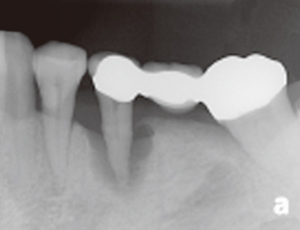

未經牙周病治療的牙齒,幾年後....

本院實例:

牙周病會造成牙齦發炎流血,齒槽骨牙周韌帶的破壞,最終導致牙齒的脫落。成人的牙齒脫落原因中有75%是因為牙周病造成的。